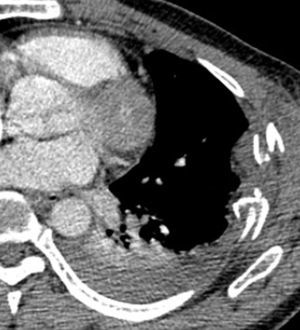

Caso 2Paciente masculino de 51 años, quien recibió trauma cerrado en hemitórax izquierdo luego de ser envestido por un toro. Recibió manejo inicial en hospital rural, pero por persistir con dolor en hemitórax izquierdo y sensación de disnea consulta a la institución. Al examen físico no se evidenció respiración paradójica, ni enfisema subcutáneo, ni hipoventilación ni agregados pulmonares. Se le tomó tomografía computada de tórax que mostró fractura desplazada de 3 arcos costales izquierdos con hemotórax; por los hallazgos clínicos y tomográficos se le practicó osteosíntesis de reja costal con el sistema STRACOS® con la utilización de sello de agua postoperatorio sin complicaciones, se incorporó a su vida laboral 20 días posteriores al trauma. No hay seguimiento de la función pulmonar por pérdida del paciente (figs. 3 y 4).